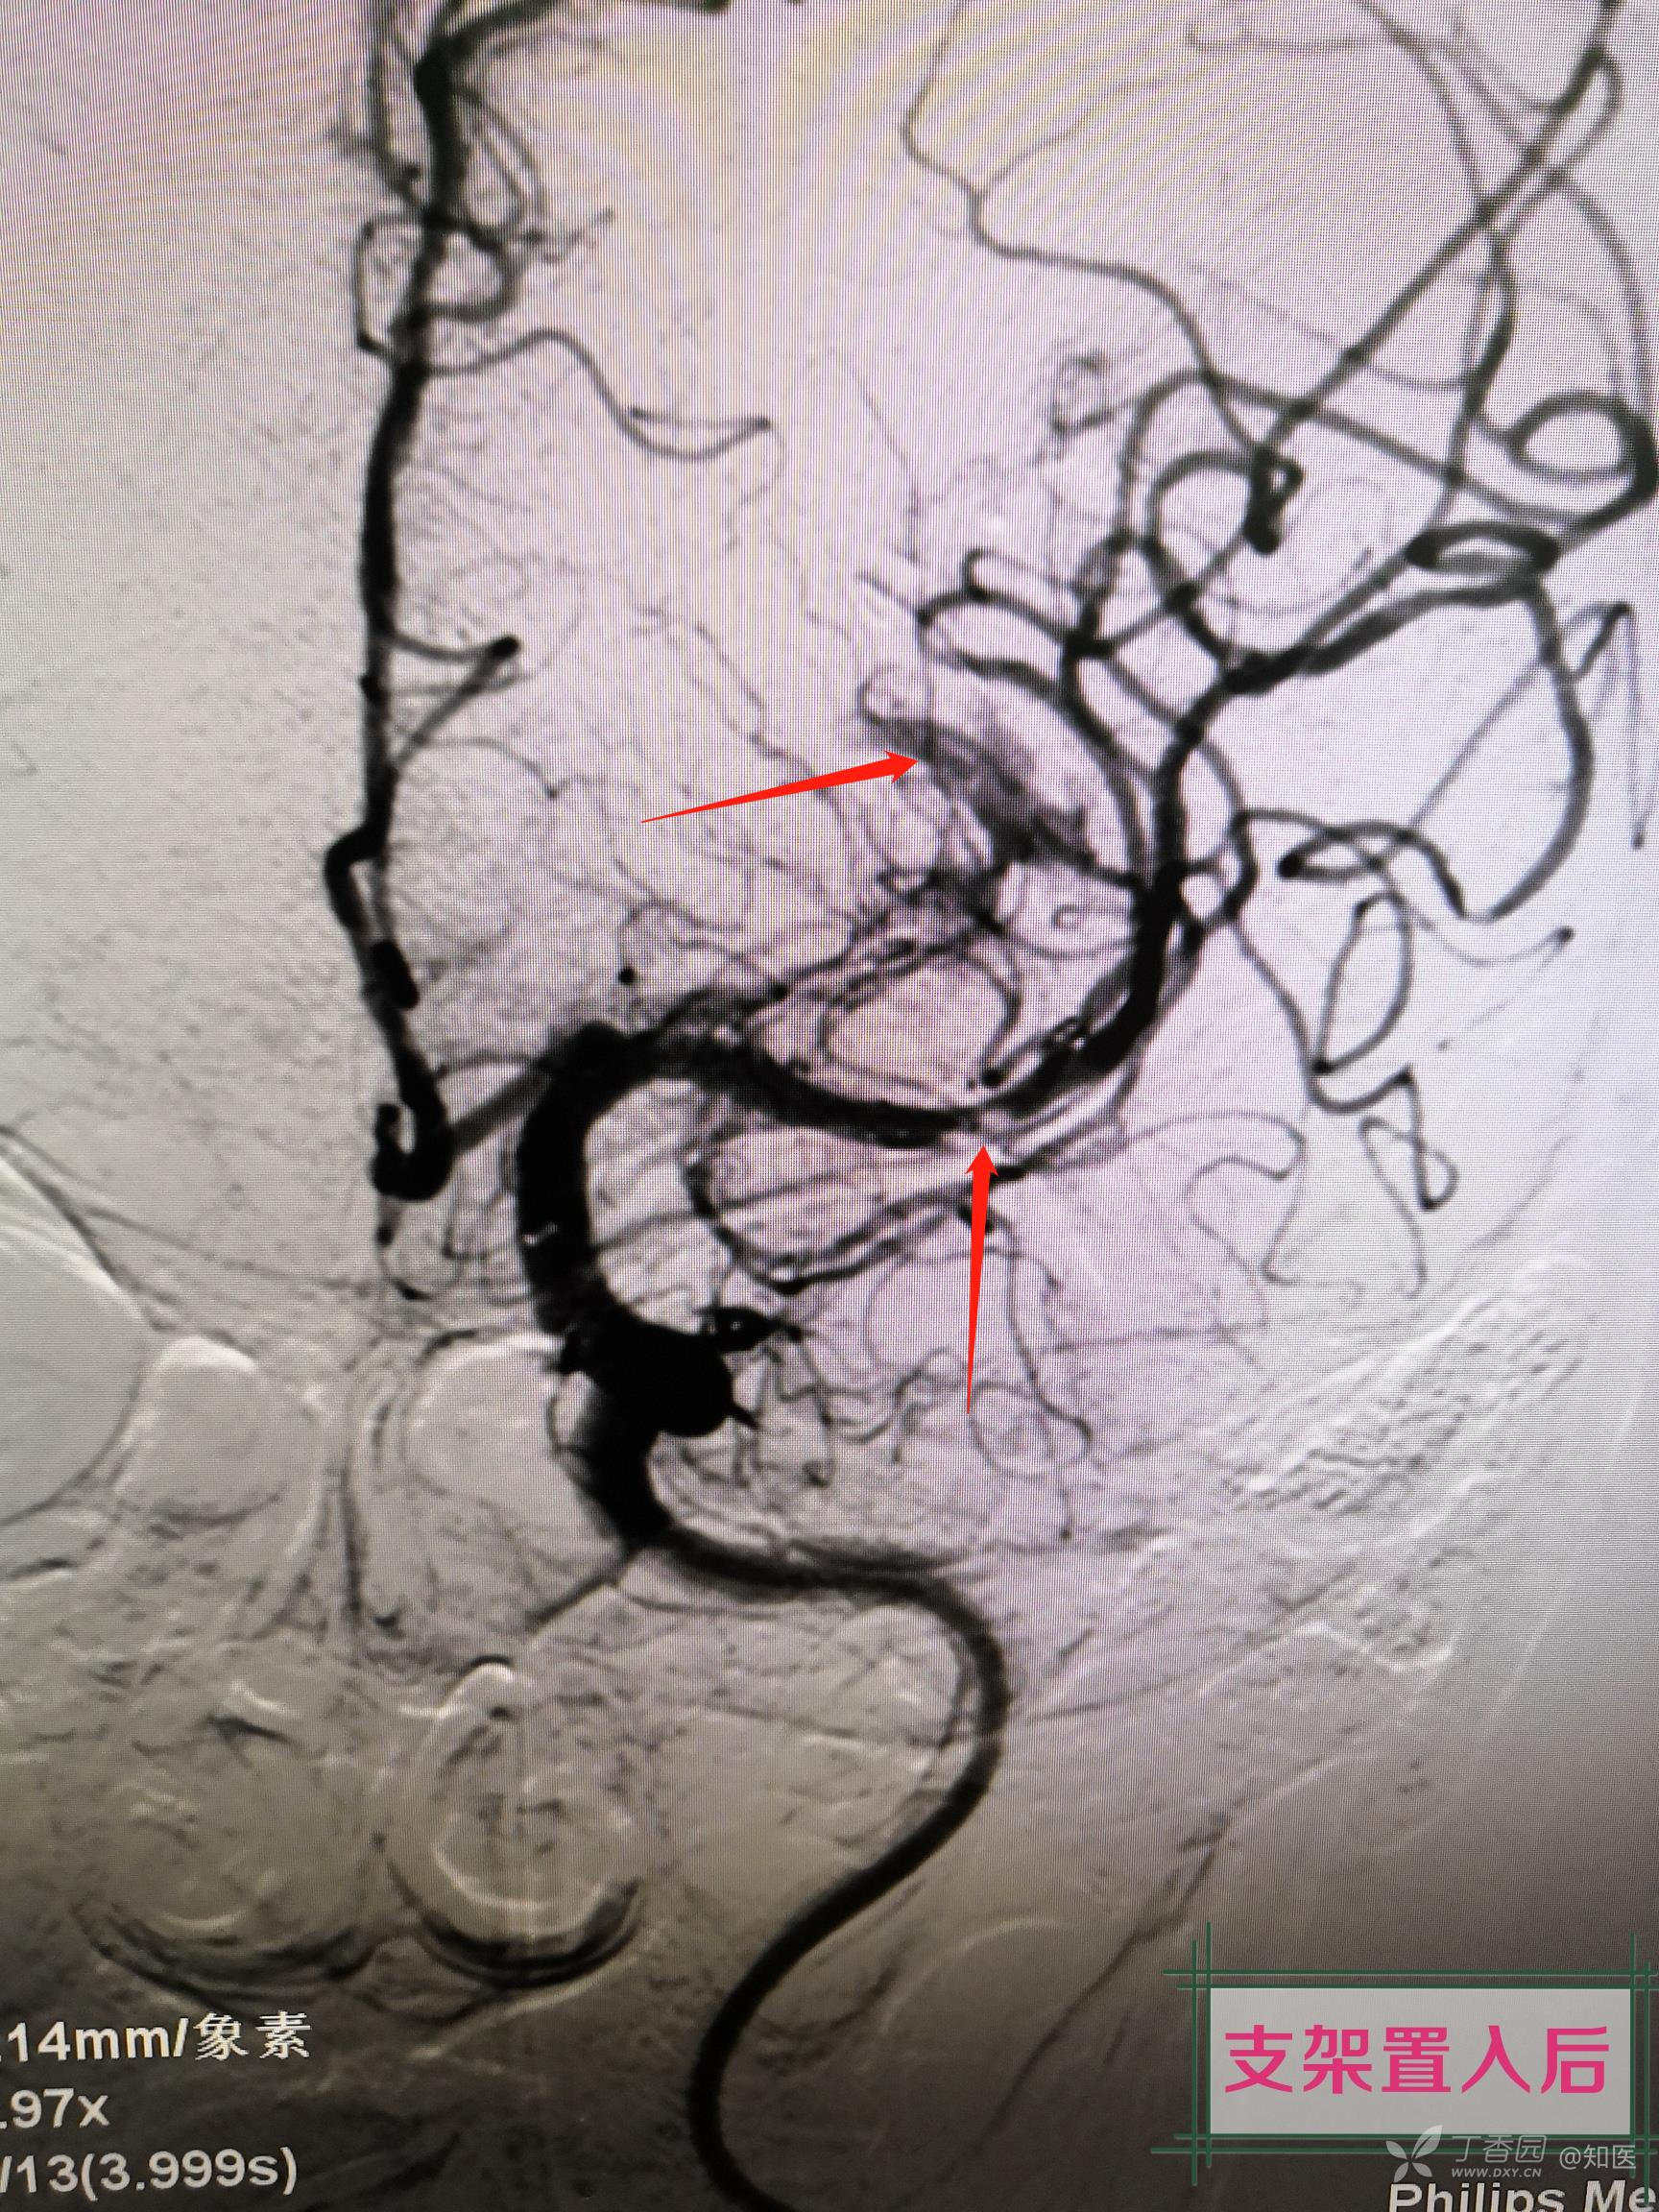

简述手术过程:采用同轴技术将8FGuiding置于左侧颈内动脉颈段,造影显示左侧大脑中动脉M2段局部白色血栓样病变,微导丝及微导管导引下将6F中间导管置于左侧大脑中接近白色血栓样病变,经中间导管尾端负压抽吸未见回血,持续负压吸引下将中间导管回撤至颈内动脉末端后,回抽未见血栓,再次造影显示左侧大脑中动脉完全闭塞,主手术者考虑血管内膜受损所致夹层闭塞。更换微导丝配合微导管通过闭塞段,将微导管置于闭塞远端,撤出微导丝,经微导管造影确认真腔,交换长导丝将1.5mm-15mm球囊置于狭窄段(局部白色血栓样病变段),给予8ATM扩张,造影见局部白色血栓样病变段90%狭窄,远端血流恢复,经导管给予欣维宁10ml,观察15min,再次造影见残余狭窄仍有90%,贴覆3.0mm-15mm支架于狭窄段,再次造影见残余狭窄约80%,支架覆盖部位造影显示仍有白色类似血栓样病变。由于多次使用及更换微导丝探测,微导丝进入左侧大脑中远端分支,远端分支血管周围可见造影剂外渗,未来得及中和肝素,患者呕吐咖啡色样胃内容物,血氧饱和度下降,心率增快,生命体征不平稳,向家属告知手术结果后终止手术。

3.球囊扩张后再次造影显示左侧大脑中远端血流恢复?

4.如果是夹层样病变,为何球扩及支架置入后局部白色血栓样病变一直存在?